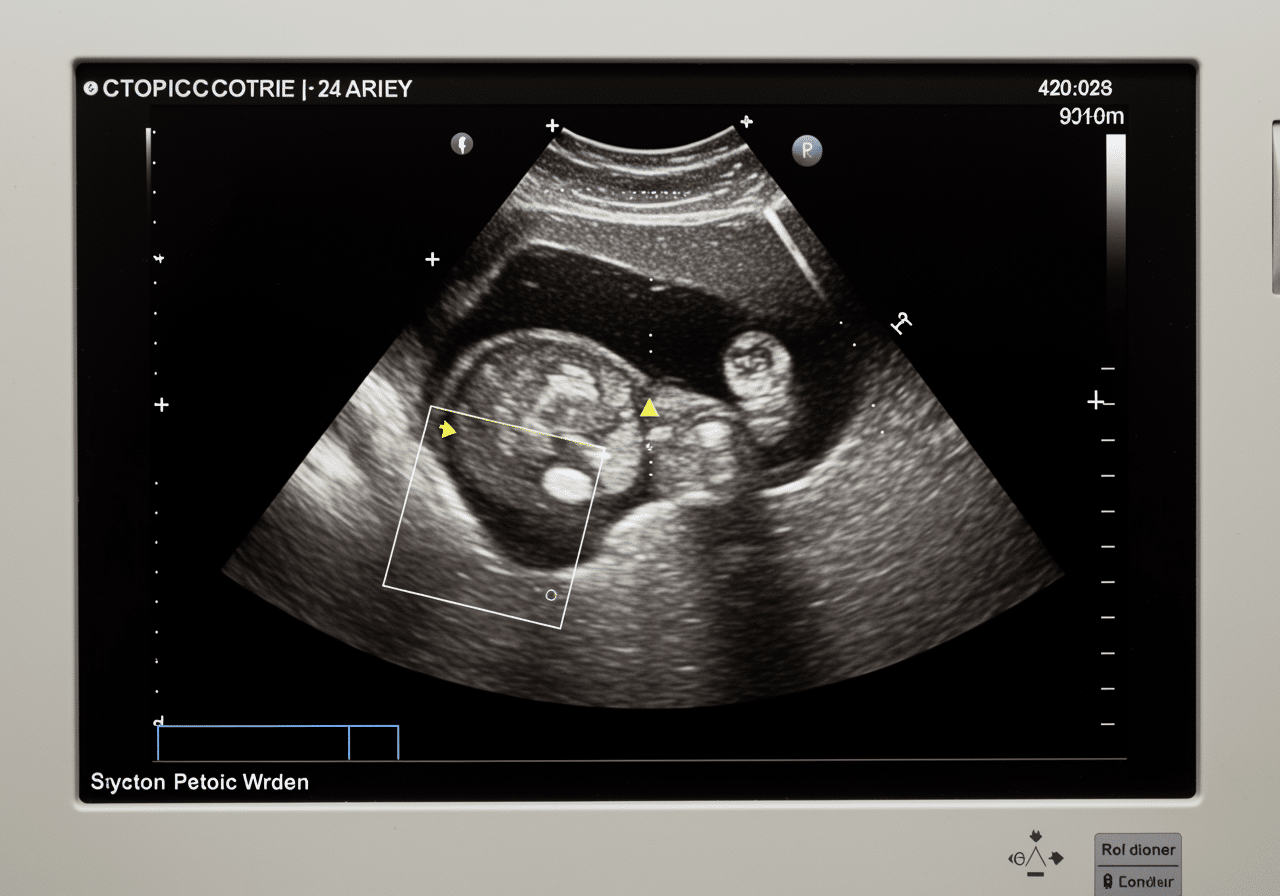

Emergency pelvic ultrasound room at Priority ER Odessa with advanced equipment

State-of-the-art pelvic ultrasound equipment available 24/7 at Priority ER for immediate gynecological evaluation